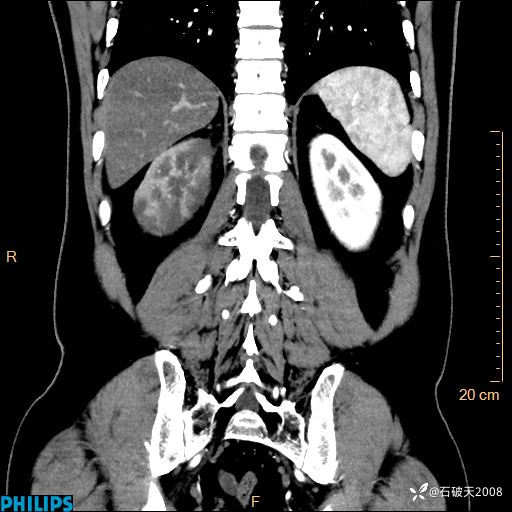

冠状位